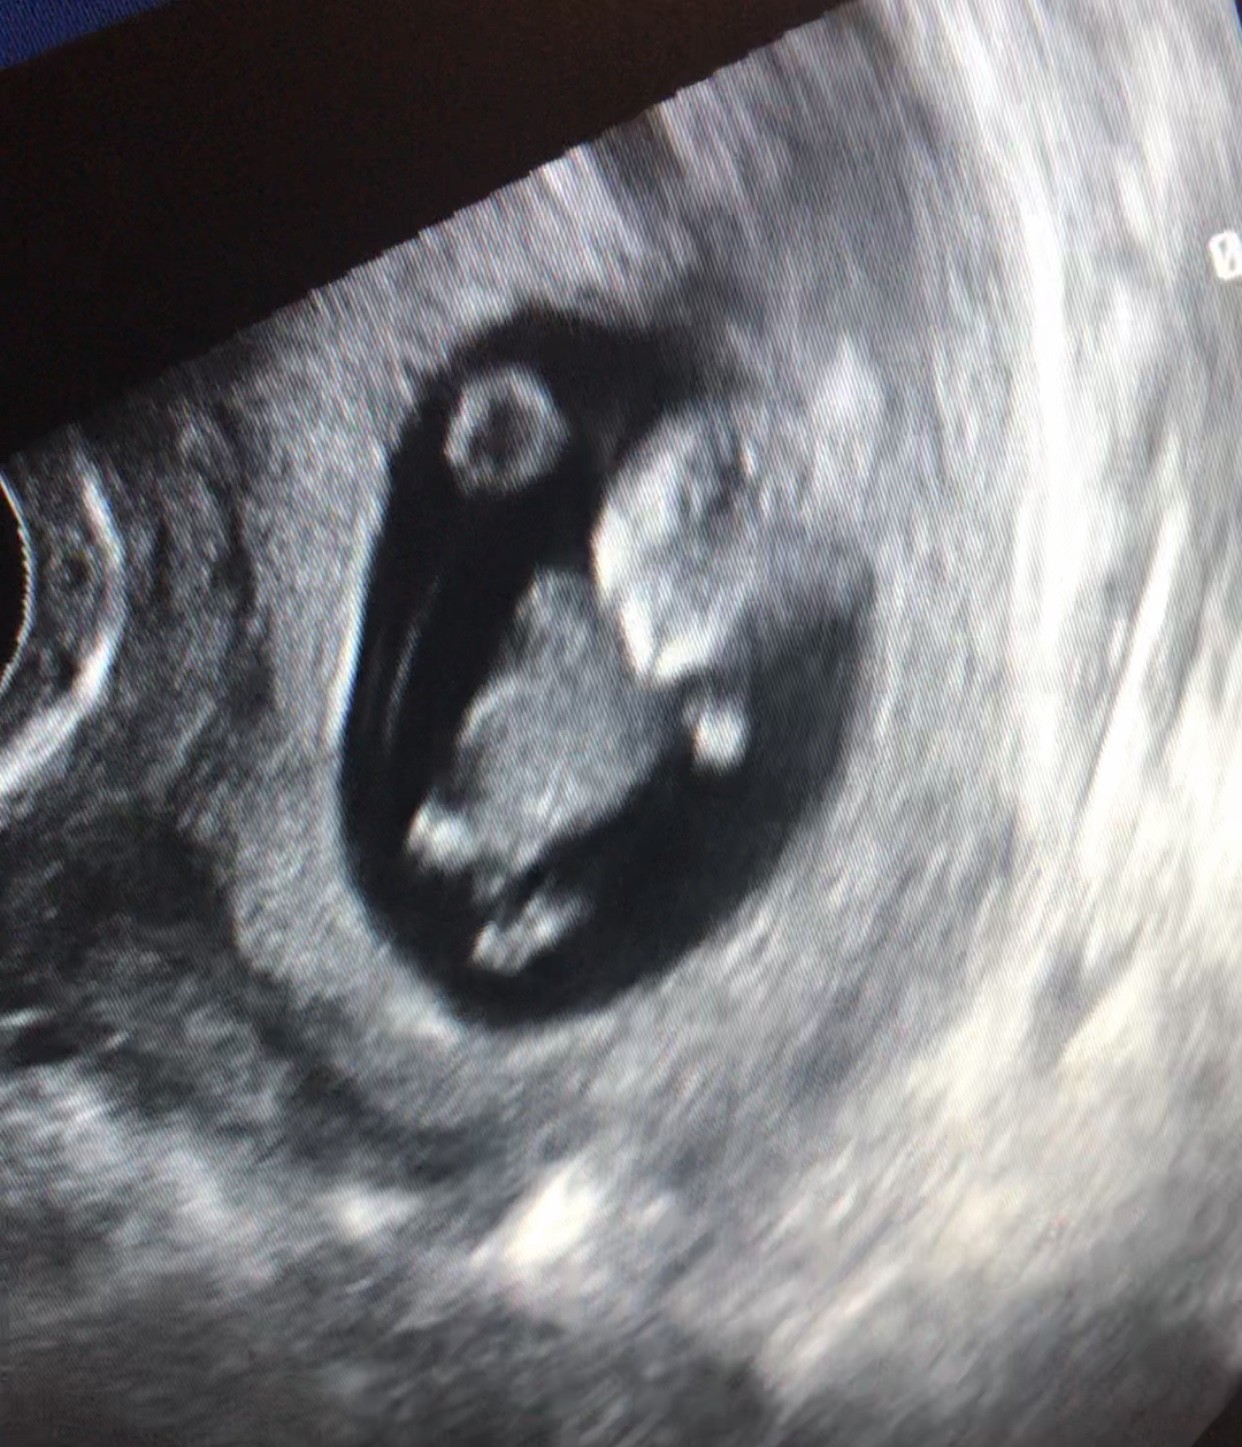

Ja już też dzisiaj po prenatalnych - wszystko idealnie!

dzidziuś już ma 6.7cm i wyszło, że 13t0d także zbliżam się do terminu z OM (teraz 06.05.21)

Bobas się ruszał jak na trampolinie